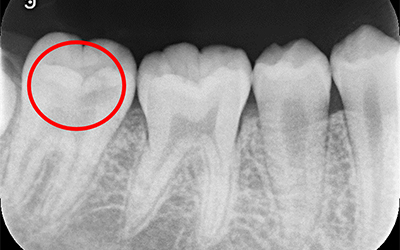

従来は、虫歯除去中に神経が見えてしまった場合は、無菌状態の神経が汚染されたと考えるのが一般的でした。

そのため、患者さん本人の痛みなどの自覚症状が無かった場合でも神経の治療をしなければなりませんでした。

しかし、現在の歯科医療では、すべての場合ではありませんが、神経を取らずに治療することができます。

それが「生活歯髄療法(VPT)」(バイタルパルプセラピー)です。

マイクロスコープで直接神経の状態を確認することです。

ポルトランドセメントを主成分とする薬で、このセメントを使う事により本来なら神経を取らざる得ない場合でも神経の保存が可能になりました。